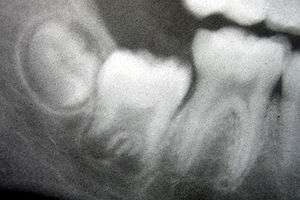

Radiograph of lower right (from left to right) third, second, and first molars in different stages of development.